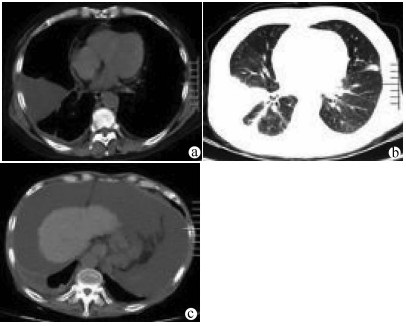

Primary hepatic carcinosarcoma with hepatocellular carcinoma: A case report

Ri LI, Huaibin GUO, Ze LIANG, Na LI, Junye WEN, Wanxing ZHANG

2021, 37(9): 2180-2182. DOI: 10.3969/j.issn.1001-5256.2021.09.034

Abstract(1261) HTML (266) PDF (4255KB)(62)

Abstract: